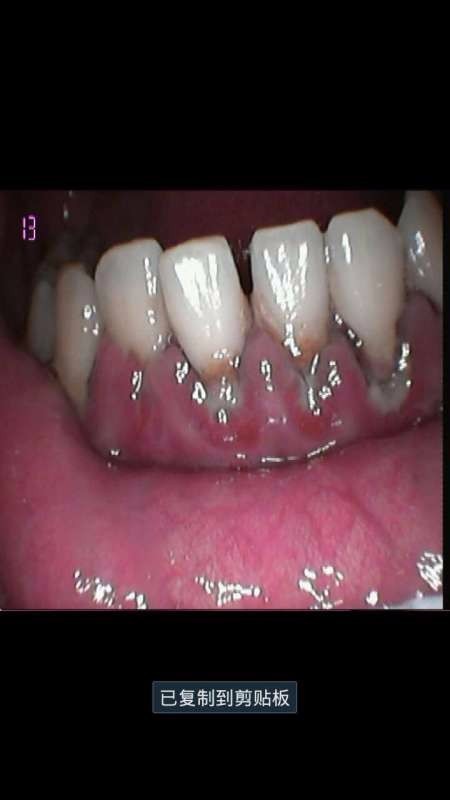

下前牙牙龈炎严重,牙龈萎缩,松3度。消炎后拔除,养好后固定桥修复